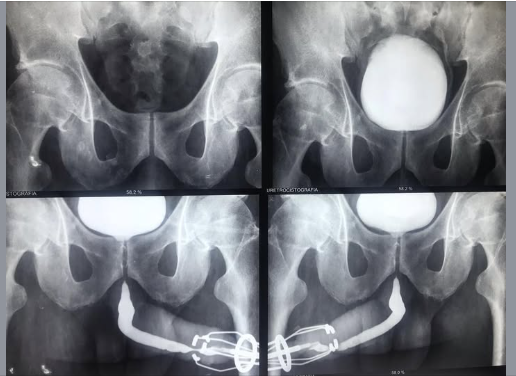

UCM Normal Masculina e Feminina

Comparativo de imagens da fase miccional em um exame normal masculino (esquerda) e feminino (direita).